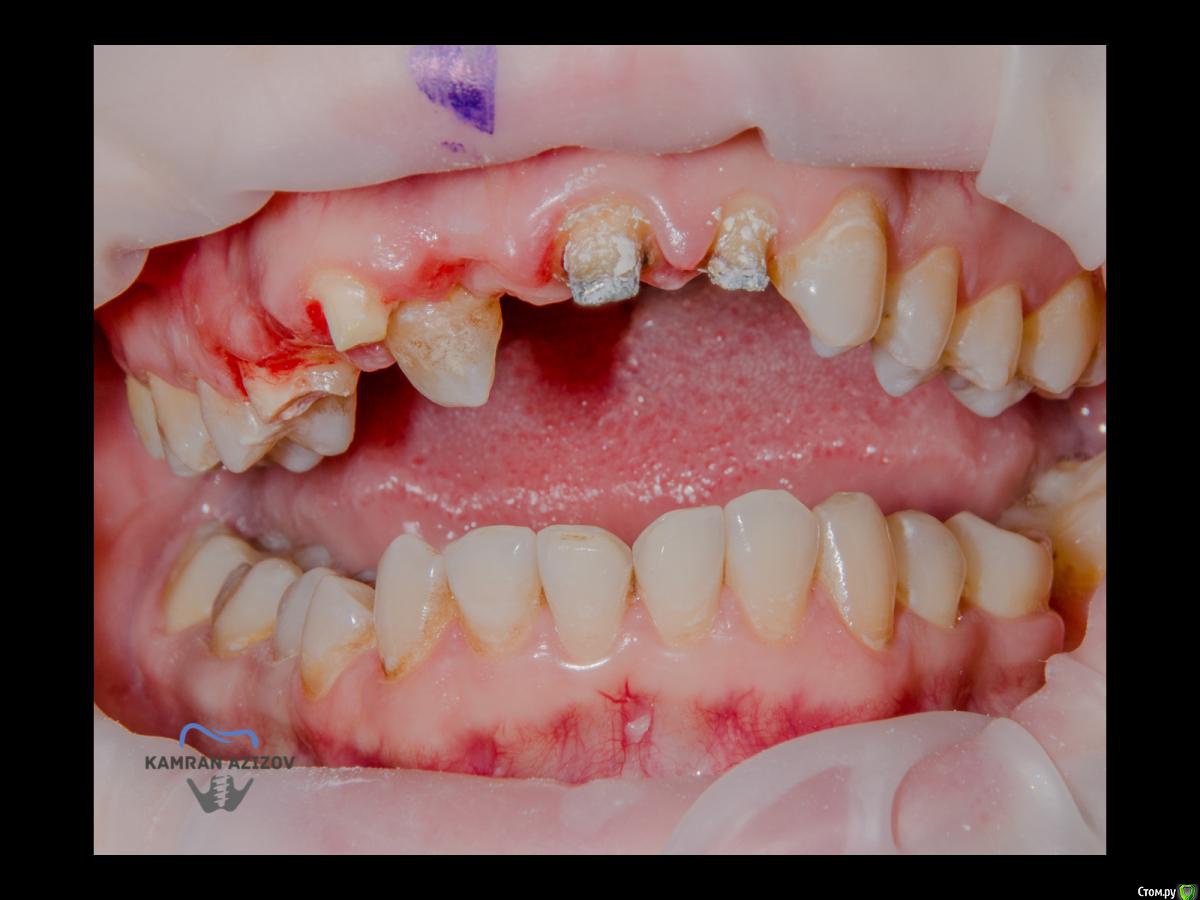

kamranchick Опубликовано 6 апреля, 2019 Поделиться Опубликовано 6 апреля, 2019 (изменено) Хай Гайсдавно ничего не комментировал и не выкладывал, что то настроения не было, да и муза не посещалаСитуация следующаяпришла пациентка, жалобы на неприятный запах из рта, сначала не понял что за хрень, ну как распилил мост понял че к чему... халтура.Ну и по кейсуУдаление клыка и 2ки, через 2 месяца навигация, имплантация + Шашлыки по карлоссу, смена формиков, временное протезирование. только мягкие ткани, Изменено 6 апреля, 2019 пользователем kamranchick 7 1 Ссылка на комментарий

kamranchick Опубликовано 8 апреля, 2019 Автор Поделиться Опубликовано 8 апреля, 2019 ТакУважаемый Петр) начнем по порядку1. пациентка отказалась от нее, как только не уговаривал ее, просто танцы с бубном были)2. после удаления клыка сразу ушел хиленький резец, делать мост 14-21-22 как то страшновато было из-за протяженности дефекта3. 1.4 зуб жалко было удалять, зачем удалять еще один зуб если так и так 2 имплантата, ну как вариант можно было бы, было бы легче позиционировать имлпнтататы4. в позиции 1.1 был большой резцовый канал, не захотелось проводить какие то манипуляции вокруг него и с ним, ну как то так)) Ссылка на комментарий

kamranchick Опубликовано 9 апреля, 2019 Автор Поделиться Опубликовано 9 апреля, 2019 kamranchick11з консоль, или это единая конструкция?13-12 с консолью на 11 Ссылка на комментарий